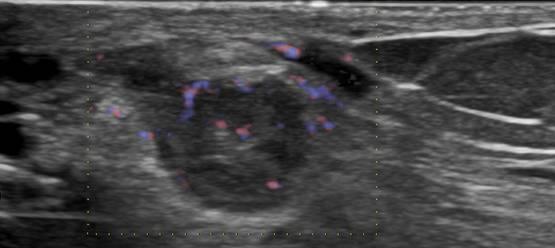

Ung thư vú

Ung thư vú - Ảnh 2

» Thông tin: Nữ giới – 69 tuổi.

» Lâm sàng: Kiểm tra sức khỏe.